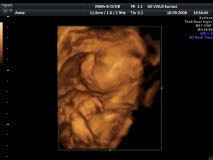

3D billeder, taget 23 uger og 5 dage

I sidste uge blev vi ringet op fra Skejby sygehus, og spurgt om vi ville deltage i et forsøg/projekt derude med 3D scanninger. Der var noget personale der skulle øve sig i at bruge sådan noget udstyr, og hvis vi ville

lægge mave til, ville vi få noget af det med hjem på billeder. Det ville vi selvfølgelig gerne, og herunder ser i noget af det vi så derude.

Og så til 3D

3D-7.jpg de små ben og fine tæer

3D-1.jpg Se hvor hun putter sig

3D-6A.jpg Hvem ligner hun? (hvem sagde moderen fordi hun ser sur ud??)

3D-5A.jpg Sød er hun da!

3D-3A.jpg Og det sidste. Hun ligger med panden ind mod moderkagen. Hun var en genert lille størrelse og var ikke meget for at blive fotograferet )

Men som I nok allerede har opdaget, sÃ¥ havde den lille ikke nogen ‘tap’ at stritte med, sÃ¥ Christian kan forvente endnu en sød og medgørelig hunkøns-Holten i huset )